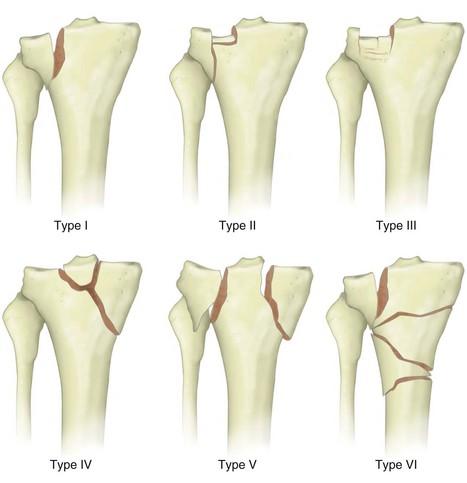

# كسور هضبة الظنبوب: التشريح، التصنيف، العلاج، والمضاعفات كسور هضبة الظنبوب هي إصابات حول مفصل الركبة تصيب الجزء العلو…

# كسور هضبة الظنبوب: التشريح، التشخيص، والعلاج كسور هضبة الظنبوب هي إصابات حول مفصل الركبة تصيب الجزء العلوي من عظم ال…

# كسور هضبة الظنبوب: التشريح الأساسي، الآلية، العلاج، والمضاعفات ## التشريح الأساسي لهضبة الظنبوب هضبة الظنبوب هي الج…